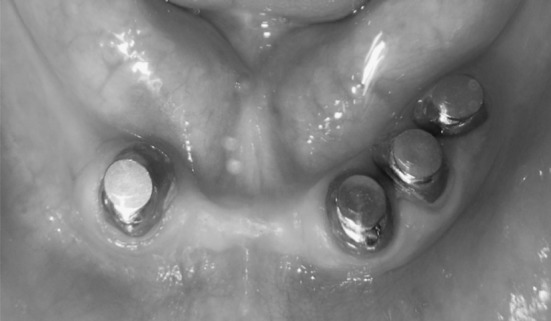

Try-In and Setting of Root Caps

All root caps were cemented on the roots teeth with glass ionomer cement (GC co; Tokyo, Japan). Excess cement was removed (Fig. 7) after cementing root caps, functional impression was made with polysiloxane impression materials (Reprosil, monophase; Dentsply International Inc, USA) under a proper pressure (Fig. 8) and definitive cast (Ultrarock, type IV dental stone; Kalabhai Karson Ltd, Vikhroli(W), Mumbai, India) was poured (Fig. 9). Now gypsum dummy (Ultrarock) was fabricated on the top of the keepers’ attractive surface of the cast so as coincided with both central axes to create space for magnetic assembly, larger than the magnetic assembly itself (Fig. 10). Now occlusal rims were fabricated on definitive upper and lower cast. Jaw relation, teeth arrangement and try- in was completed on waxed denture (Fig. 11) and processed. All interceptive occlusal contacts were eliminated before fixing the magnetic assembly in intaglio surface of overdenture.

Fig. 7.

Keepers along with post were cemented with resin cement